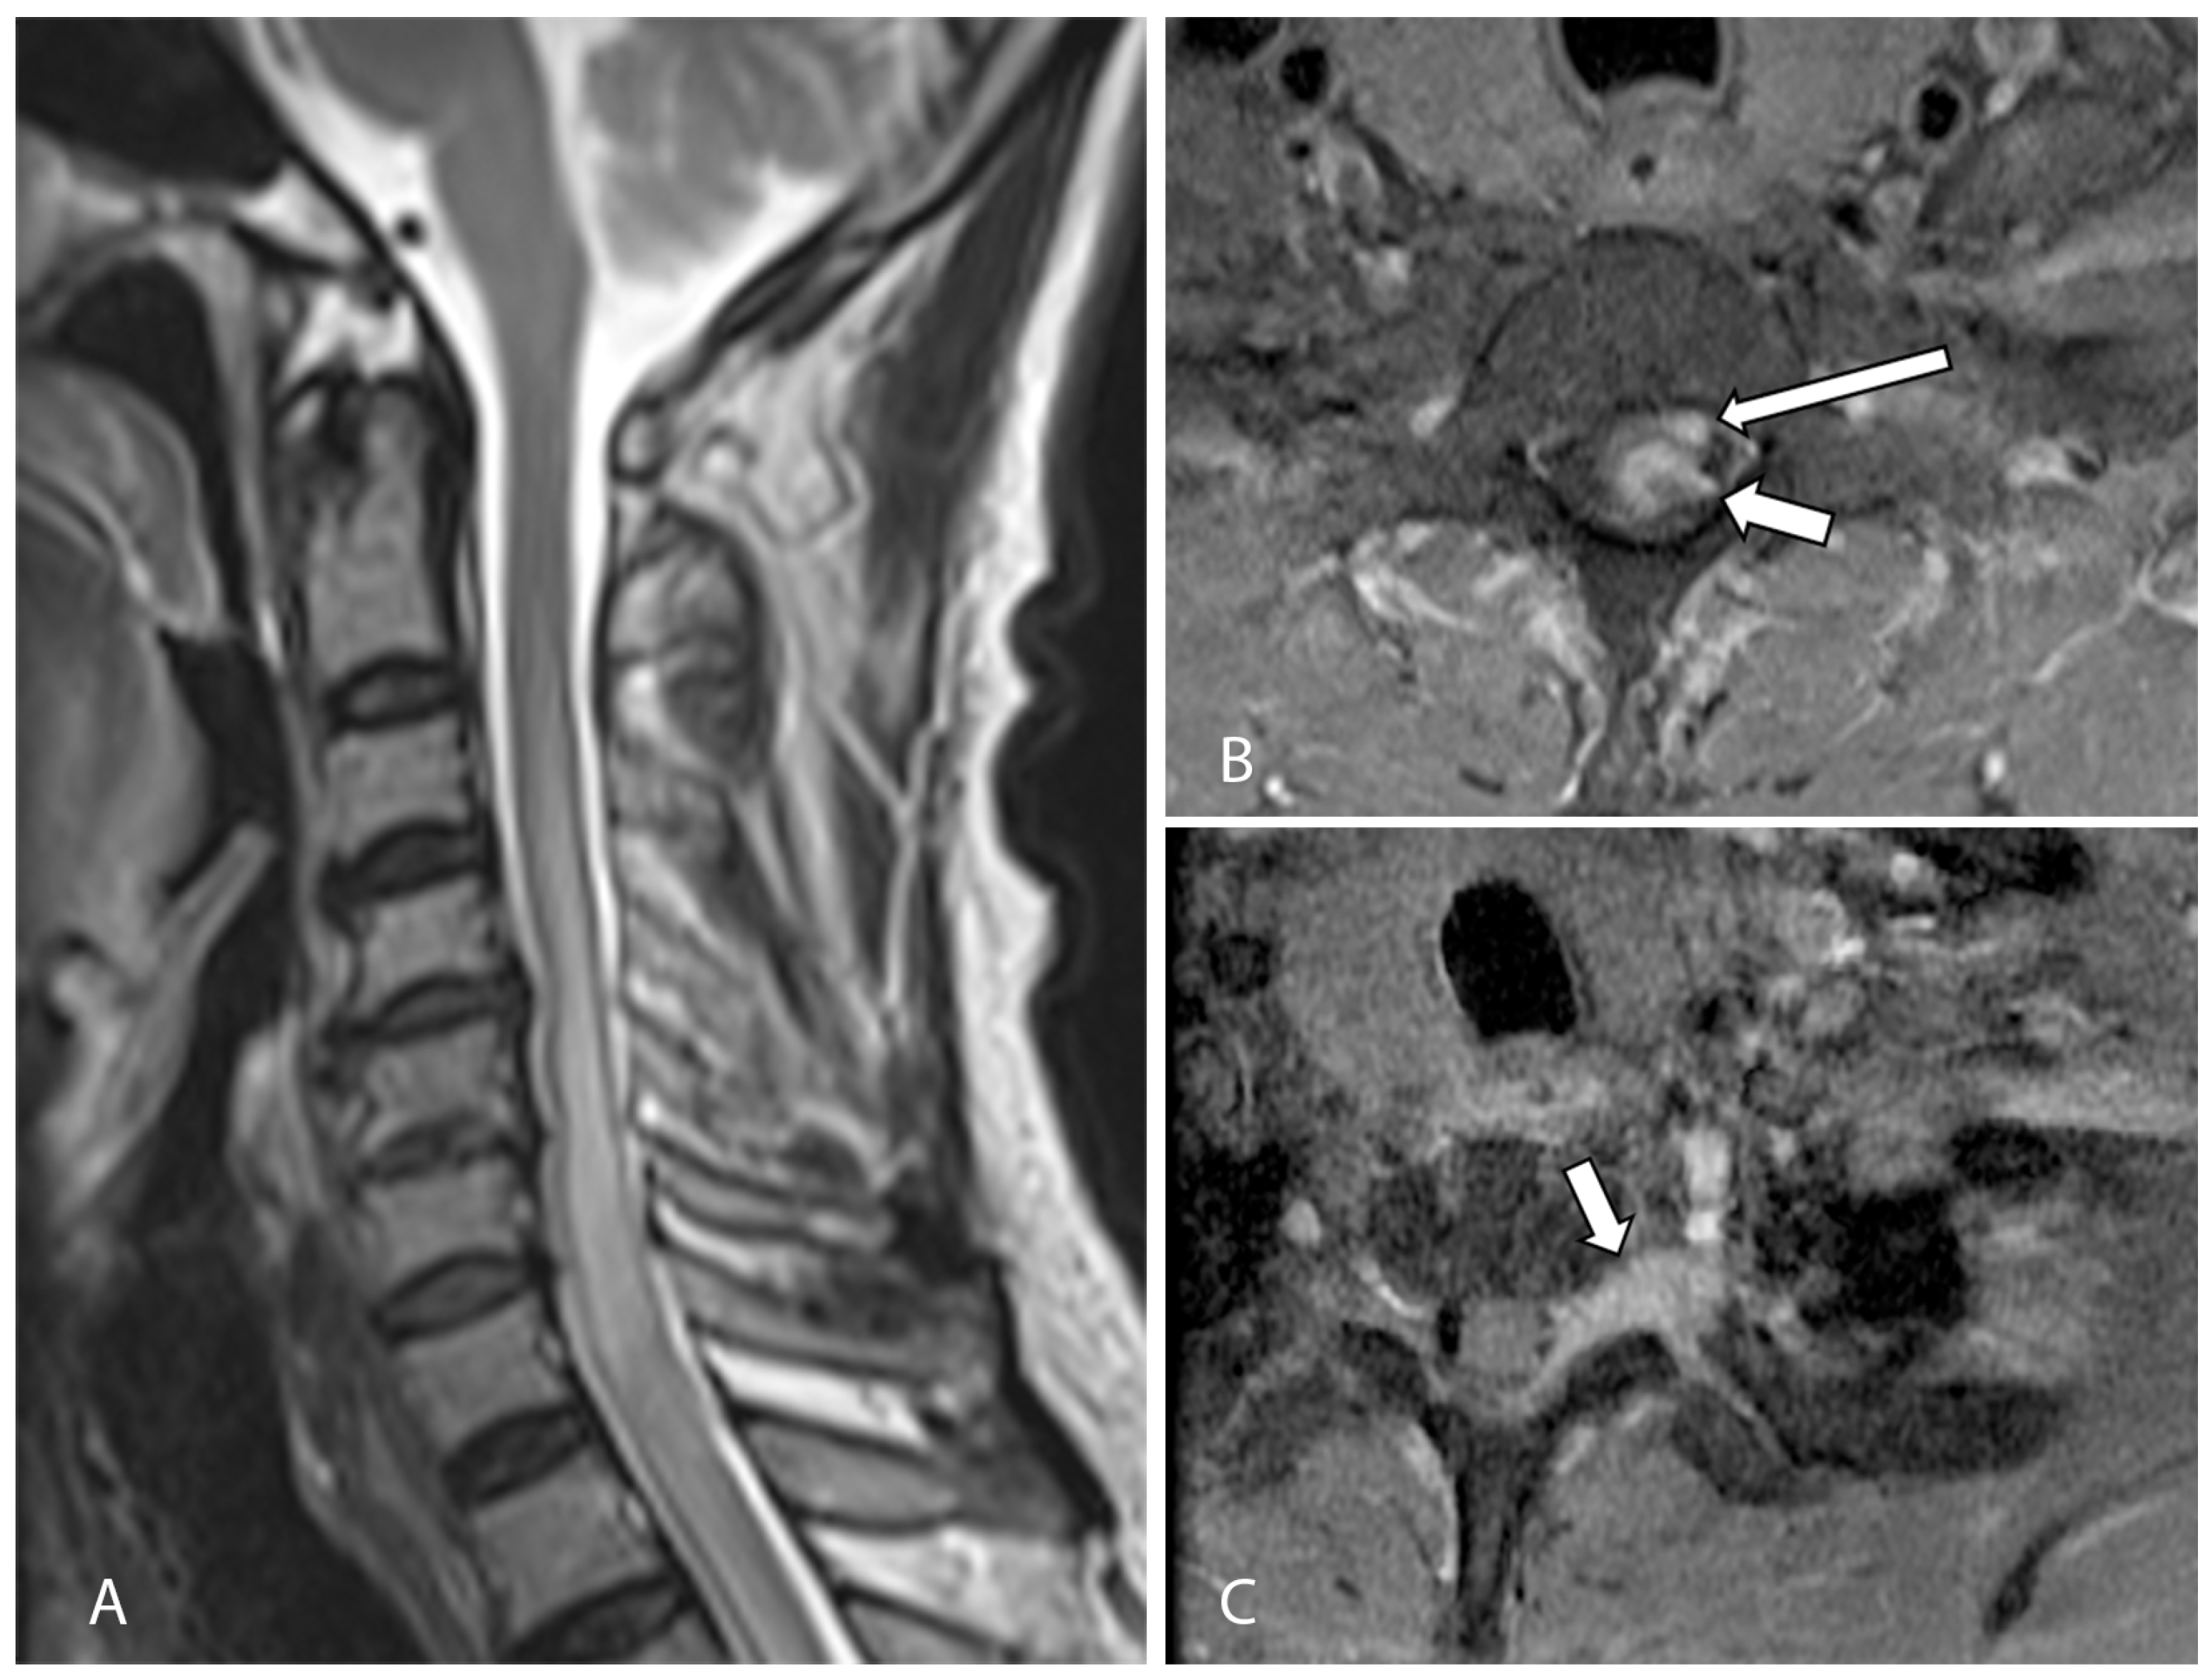

2. Case Presentation